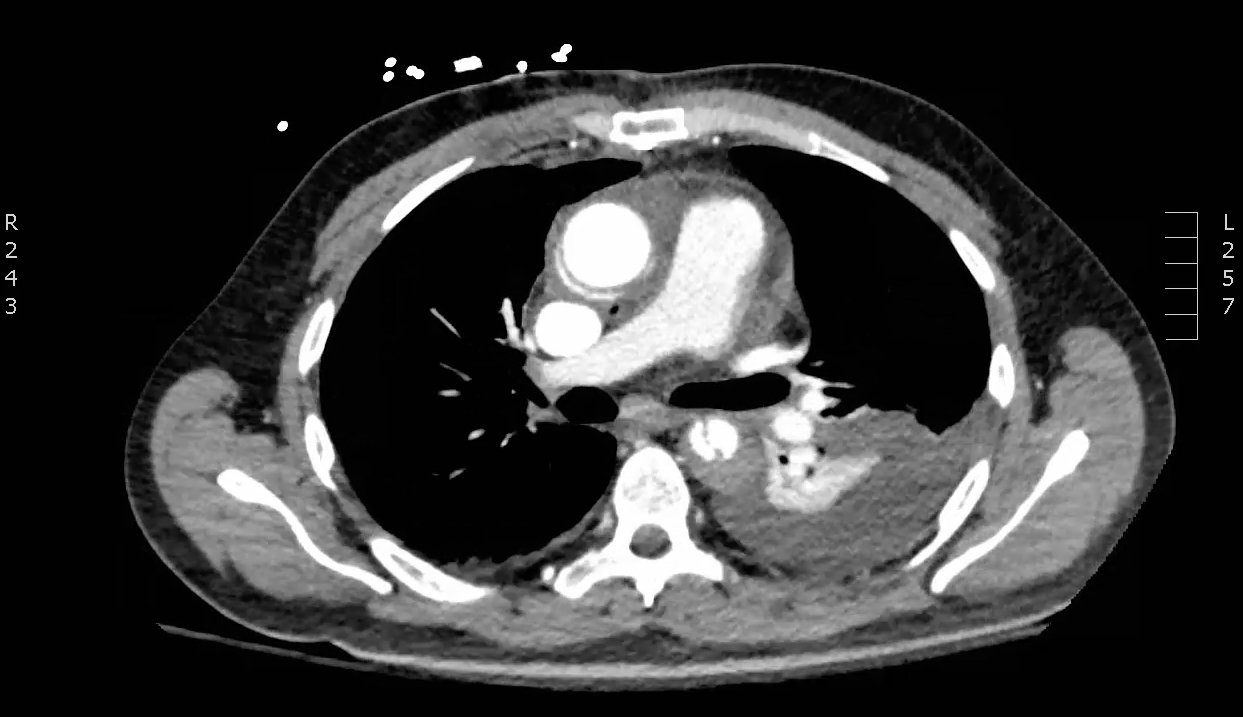

Chest x-ray and CT angiogram was performed to evaluate his thoracic and abdominal vasculature. Chest x-ray did not show any significant widening of the mediastinum. The CT angiogram demonstrated an intimal tear along the aortic arch separating a true and false aortic lumen, consistent with an acute aortic dissection. The true lumen (highlighted in blue in images 1-5) can be identified by continuity with an undissected part of the aorta1. While the false lumen (highlighted in red in images 1-5) can be identified by its crescent shape and larger cross-sectional area.1